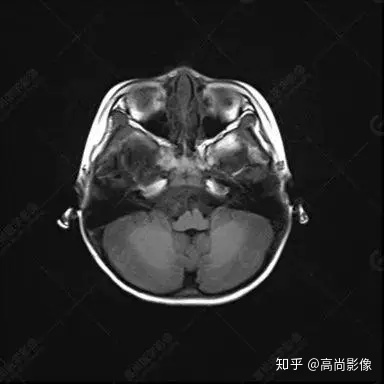

右側(cè)顳葉腫瘤切除術(shù)后(具體不詳):右側(cè)顳部骨質(zhì)不連續(xù)呈術(shù)后改變,右側(cè)顳葉術(shù)區(qū)見片狀長(zhǎng)T1長(zhǎng)T2信號(hào)影,F(xiàn)LAIR呈低信號(hào);術(shù)區(qū)后方右側(cè)顳枕葉見一巨大占位性病變影,邊界欠清,大小約6.2×5.8×4.3cm(前后×左右×上下),信號(hào)不均勻,T1WI呈等稍低信號(hào)間雜少許高信號(hào),T2WI呈高稍低混雜信號(hào),DWI示部分病灶彌散受限,相應(yīng)ADC圖減低,磁敏感序列見部分呈極低信號(hào),增強(qiáng)掃描可見明顯不均勻強(qiáng)化,鄰近硬腦膜及小腦幕增厚并明顯強(qiáng)化;另延髓右前方及右側(cè)橋小腦角區(qū)見一不規(guī)則形異常信號(hào)影,大小約3.2×1.3×3.7cm(左右×前后×上下),呈長(zhǎng)T1稍長(zhǎng)T2信號(hào),F(xiàn)LAIR呈等信號(hào),DWI未見受限,增強(qiáng)后明顯均勻強(qiáng)化,鄰近腦膜明顯強(qiáng)化。鄰近腦實(shí)質(zhì)及右側(cè)顳角明顯受壓;左側(cè)大腦半球未見局灶性信號(hào)異常,中線結(jié)構(gòu)稍左移。

右側(cè)顳葉腫瘤切除術(shù)后:現(xiàn)術(shù)區(qū)后方右側(cè)顳枕葉及延髓右前方占位,右側(cè)顳枕部硬腦膜及小腦幕明顯強(qiáng)化,結(jié)合既往影像資料,考慮為胚胎源性惡性腫瘤,如非典型畸胎樣/橫紋肌樣瘤(AT/RT)或原始神經(jīng)外胚層腫瘤(PNET)。